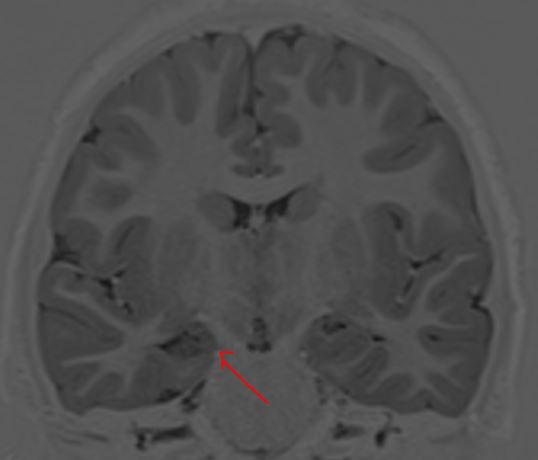

In the coronal T1 weighted image above, the body of the right hippocampus is atrophic, with reduced signal within the same hippocampus, predicting neuronal loss and spongiosis. in this example, the hippocampal atrophy likely is a consequence of the seizure disorder, rather than the cause. Furthermore, the symptomatology of the seizures is primarily of motor seizures, typically tonic-clonic with some motor asymmetries implicating the right hemisphere. However, it is the absence of a history of temporal lobe seizures that is equally important.  Then there is the interictal EEG recording: